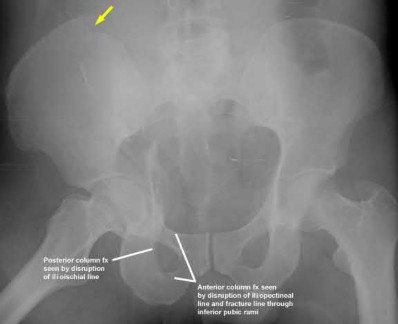

Figures A-C: The initial radiographs reveal the posterior subluxation of the talus with associated posterior subluxation of the fibula without significant coronal plane deformity. This deformity should raise the suspicion of a Bosworth fracture-dislocation, especially if closed reduction is not successful. Figures D and E: Axial CT images demonstrating Bosworth fracture-dislocation of the fibula entrapped behind the tibia. Also, note the fracture extension to the posteromedial rim in this posterior pilon variant.